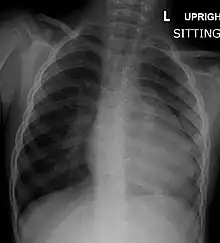

| Right ventricular hypertrophy | The right ventricle is more muscular than normal, causing a characteristic boot-shaped (coeur-en-sabot) appearance as seen by chest X-ray. Due to the misarrangement of the external ventricular septum, the right ventricular wall increases in size to deal with the increased obstruction to the right outflow tract. This feature is now generally agreed to be a secondary anomaly, as the level of hypertrophy tends to increase with age.[44] |

Before more sophisticated techniques became available, chest X-ray was the definitive method of diagnosis. The abnormal "coeur-en-sabot" (boot-like) appearance of a heart with tetralogy of Fallot is classically visible via chest X-ray, although most infants with tetralogy may not show this finding.[49] The boot like shape is due to the right ventricular hypertrophy present in TOF. Lung fields are often dark (absence of interstitial lung markings) due to decreased pulmonary blood flow.[50]: 171–72